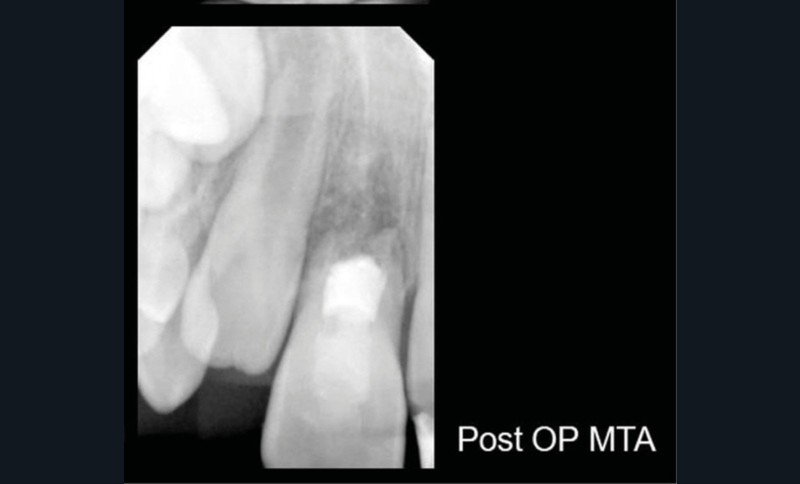

Ce cas clinique est particulier et illustre parfaitement l’évolution que suit l’endodontie depuis une dizaine d’années. Sans entrer dans le détail technique, cette dent expulsée avait été repositionnée dans son alvéole et un premier traitement de régénération intracanalaire tenté. Malheureusement suivi d’un échec. Le jeune âge de la patiente a été une motivation particulière pour tout tenter dans le but, au moins, de gagner du temps. Après plusieurs séances d’hydroxyde de calcium, l’apexification a été réalisée comme cela était possible. Le contrôle à 18 mois confirme que l’acharnement a payé.

Plus que sur l’éventuelle « prouesse technique » – qu’en tant que praticien nous pouvons être tentés de saluer –, il faut s’arrêter sur la facilité qu’a la biologie de stabiliser une situation pourtant désespérée, lorsque les conditions de remise en conditions saines sont mises en place.